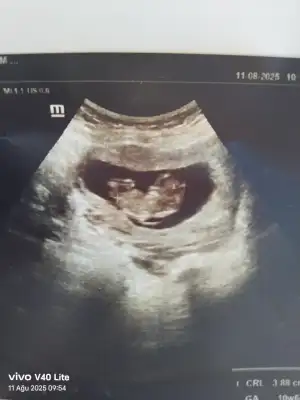

Benim attığımı da tahmin eder mısınız 11+5Bariz erkek görüyorum, sağlıcakla gelsin inşallah![]()

Erkek görüyorum sağlıcakla gelsin inşallahBenim attığımı da tahmin eder mısınız 11+5

Ay erkek demişiim, kız görüyorum olacaktııErkek görüyorum sağlıcakla gelsin inşallah![]()

Ben hep kız hissettim hiç beklemiyordum açıkçası sürpriz oldu bana daAy erkek demişiim, kız görüyorum olacaktıı

İki çizgi olması kız ama nub'u bir tık yukarı doğru erkek mi acaba derken kız yerine erkek yazmışımnub'u dik de olsa o çizgiler birbirinden ayrı olursa %90 kız oluyor

Annenin içine doğan olur genellikle, benim size cinsiyet tahminim de kıızBen hep kız hissettim hiç beklemiyordum açıkçası sürpriz oldu bana daama detaylı ultrason da farklı çıkabiliyormus onu da bir bekleyelim dedi doktor değişme ihtimali olur mu hiç bilmiyorum ama

Doktor çok emindi aslında kesin dedi ama ben emin olamayınca öyle dedi bakalım sağlıklı olsun daAnnenin içine doğan olur genellikle, benim size cinsiyet tahminim de kıızilk başta erkek diye yanlış yazmışım